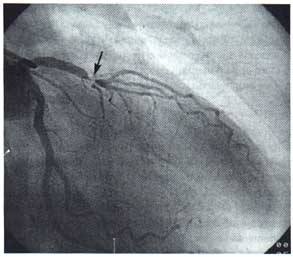

对于稳定性心绞痛,治疗重点在于稳定粥样斑块和抗血小板治疗。他汀类药物降低胆固醇和低密度脂蛋白,还能稳定粥样斑块。阿司匹林等抗血小板药物也是常用药物。另外根据病情使用其它药物。对于不稳定心绞痛,一定要做冠状动脉造影,了解有没有明显的狭窄,必要时冠状动脉支架置入,或者外科搭桥手术。

对于急性心梗的患者,一定要尽快再通堵塞的冠状动脉,3小时内可以选择溶栓治疗,超过3小时冠状动脉支架置入是最重要的治疗手段。